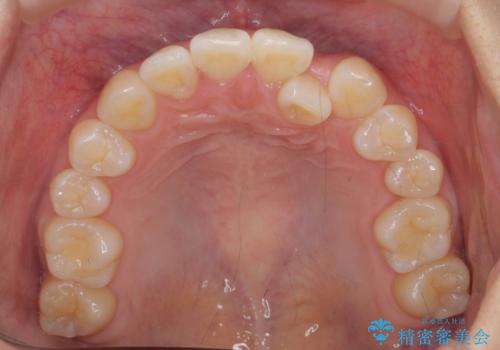

- 噛んだ時の前歯正中のズレ、引っ込んでいる前歯を治したい。と矯正治療を希望され来院されました。

左上2の前歯はスペースが足りないため、後方に引っ込んでしまっている状態です。